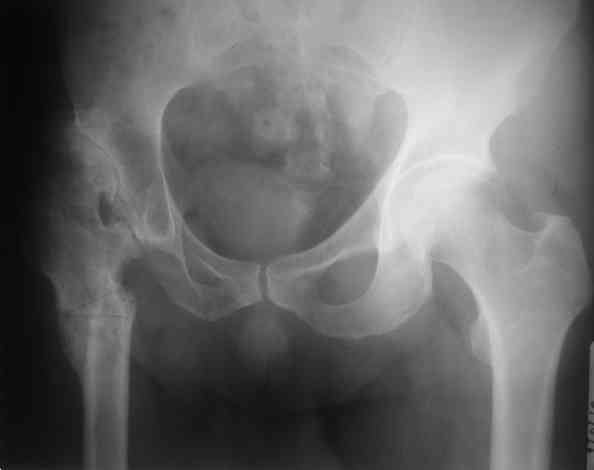

Был у нас подобный случай

Выполнена одномоментная коррекция деформации, эндопротезирование DePyu Pinnacle-AML. Пластинка с деротационной целью. При использовании ножки с прямоугольным сечением, думаю, можно и без нее.